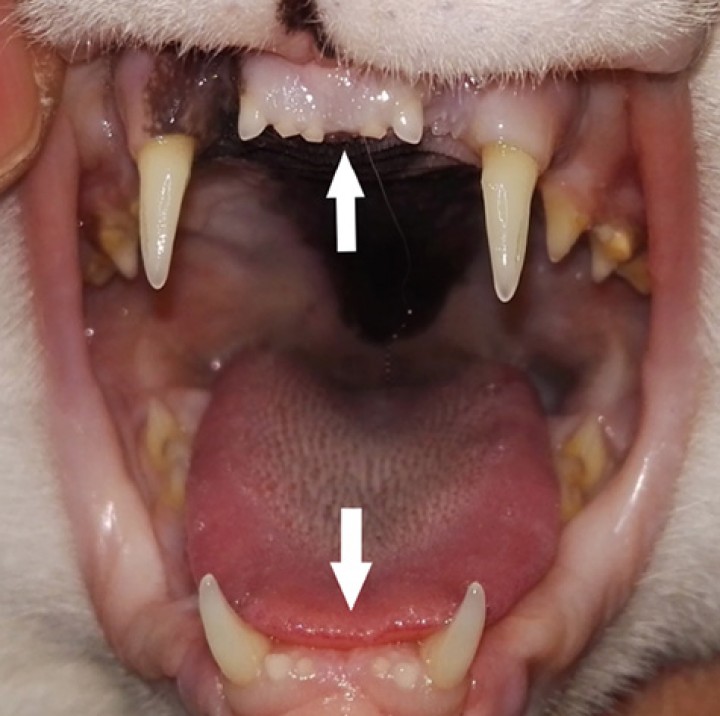

<p>Ausencia aparente de 201, 301, 401 (primeros incisivos maxilar izquierdo, mandibular izquierdo y derecho) (flechas).</p>

Ausencia aparente de 201, 301, 401 (primeros incisivos maxilar izquierdo, mandibular izquierdo y derecho) (flechas).